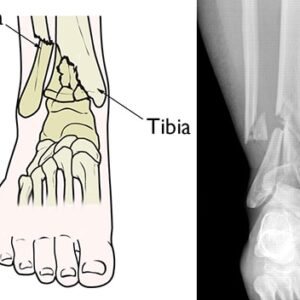

Foot & Ankle Patient informationPilon fractures are a distinct type of injury affecting the lower end of the tibia (shinbone), specifically involving the weight-bearing surface of the ankle joint. These fractures often extend to the fibula, the other bone in the lower leg. Typically resulting from high-impact incidents such as motor vehicle accidents or